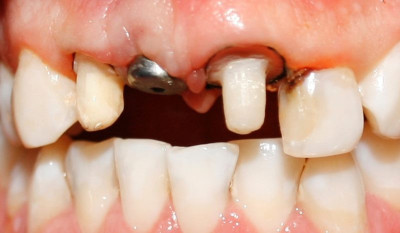

Antes

Frente inicial se planifica rehabilitación de frente estético combinando endodoncia implante